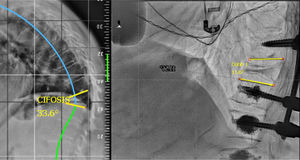

Dentro del grupo de la deformidad local (estadio 1), esta puede ser flexible (1A), si se observa una reducción de la angulación mayor del 50% en el decúbito con respecto a la radiografía (fig. 2) en bipedestación o rígida (1B), cuando no se ve una reducción con el decúbito (fig. 3)13. Por último, esta deformidad local, puede estar compensada (C) cuando la teleradiografía en bipedestación el SVA está en parámetros normales, o no compensada (NC), cuando la teleradiografía demuestra un SVA fuera de rango. Conviene recordar que el SVA está ajustado a la edad, y no buscamos una corrección tan exigente en el paciente anciano como en el paciente joven8.

En el grupo de cifosis angular flexible compensada (1A C), si presenta un trazo estable se puede realizar una vertebroplastia (VP)/cifoplastia (KP) para hacer una corrección de la cifosis flexible y dar estabilidad anterior. En caso de una afectación del muro posterior o fractura de pedículos, que traduzcan inestabilidad, habría que añadir una instrumentación cementada corta para aportar la estabilidad7. En el caso de que la cifosis angular flexible no está compensada (1A NC) y exista un desequilibrio sagital por hipercifosis torácica proximal, pueden ser necesarias osteotomías de Ponte o de flexibilización facetaria y sería necesaria la instrumentación larga hasta la columna torácica alta (T2-5) para prevenir la patología del nivel adyacente (fig. 5).

Ilustración de un caso con estadio 1ANC, en el que sin necesidad de realizar una osteotomía tricolumnar se observa una muy buena reducción intraoperatoria y se realiza una instrumentación larga percutánea T4-L2 y vertebroplastia de L3, L4 y L5 por presentar fracturas a dicho nivel.1 ANC: deformidad secundaria a fractura vertebral osteoporótica Angular, Flexible y No Compensada.